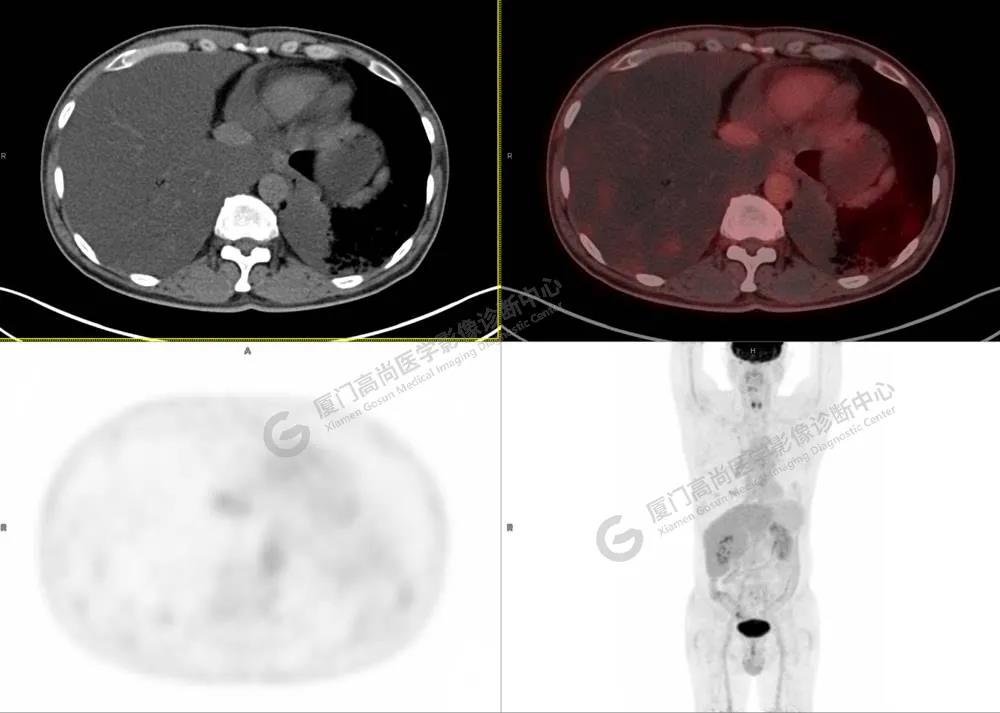

PET/CT影像圖

圖3

圖4

PET/CT所見(jiàn):雙肺大片實(shí)變影及磨玻璃影,部分呈地圖樣改變,累及右肺尖,部分放射性攝取輕微增高,SUVmax 1.77,其內(nèi)見(jiàn)多發(fā)支氣管充氣征象。

影像診斷: 雙肺大片實(shí)變影及磨玻璃影,大部分代謝不高,局部代謝輕微增高,考慮肺泡蛋白沉積癥,建議病理學(xué)檢查或肺泡灌洗物檢查。